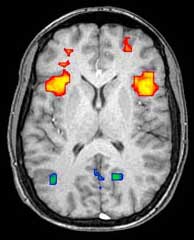

التصوير بالرنين المغناطيسي الوظيفي

Axial MRI slice at the level of the basal ganglia, showing fMRI BOLD signal changes overlayed in red (increase) and blue (decrease) tones.